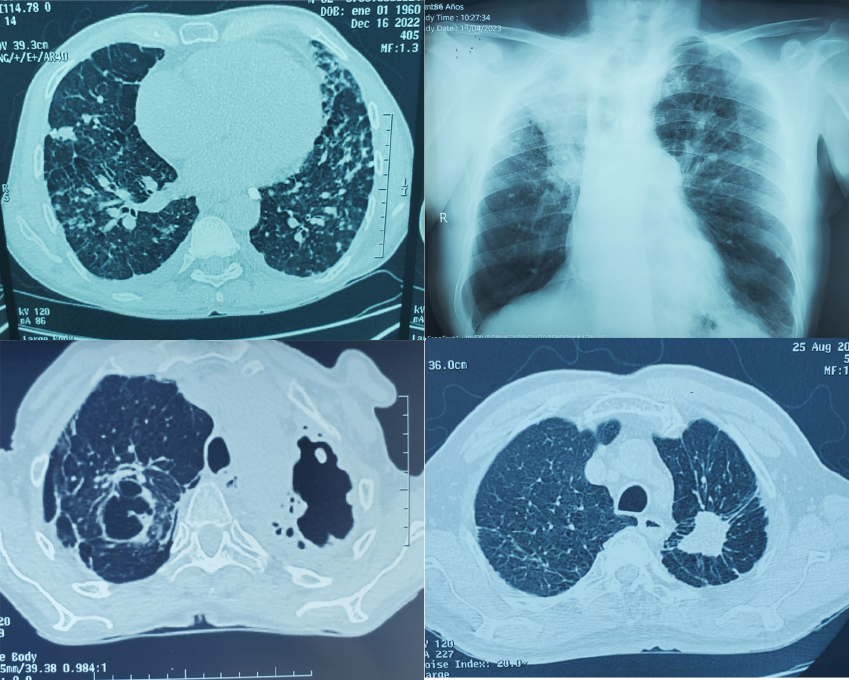

Figura 4.

Hallazgos radiológicos secundarios encontrados en los pacientes con antracosis. A: TAC de tórax corte axial ventana pulmonar que muestra múltiples nódulos bilaterales asociados a patrón reticular y engrosamiento pleural posterior derecho. B: Rx PA de tórax que muestra atelectasia del lóbulo superior derecho. C: TAC de tórax corte axial en ventana pulmonar que muestra cavitaciones apicales bilaterales. D: TAC de tórax corte axial en ventana pulmonar que muestra masa espiculada sin bordes definidos en lóbulo superior izquierdo.